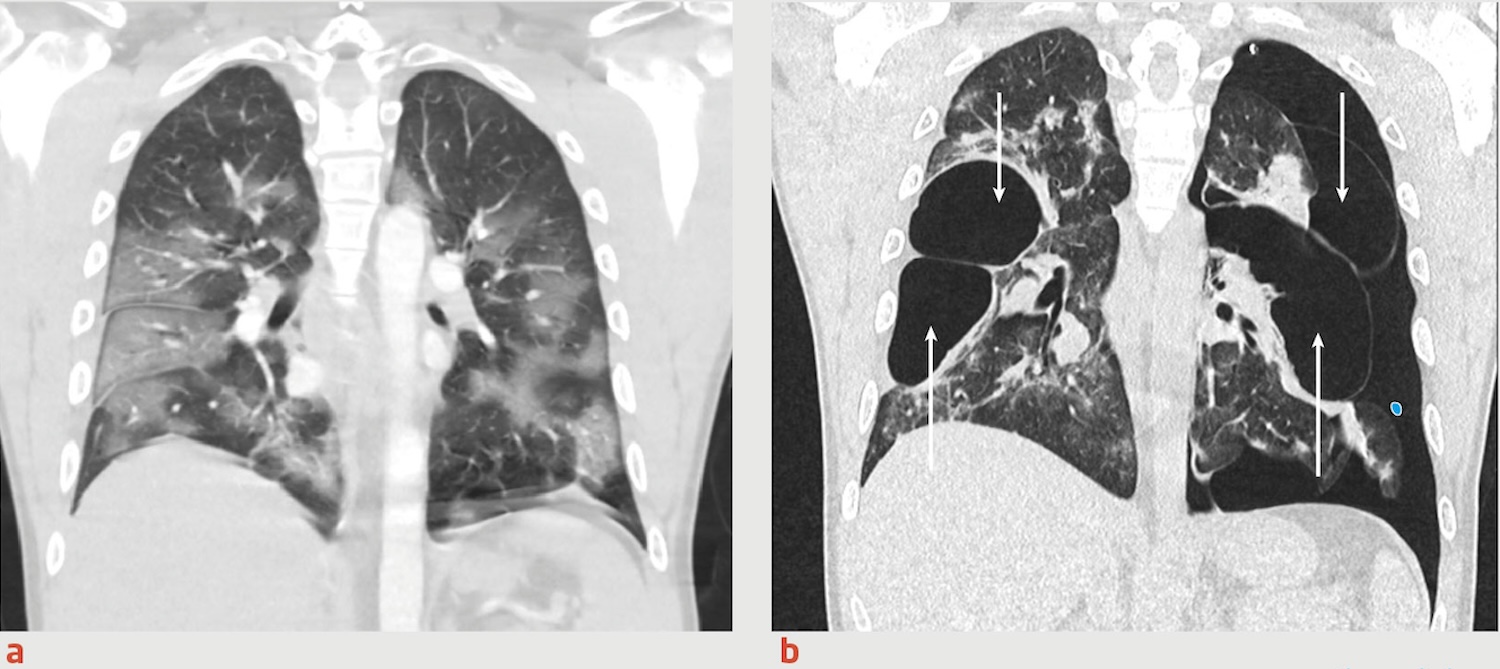

Tijdens de onderzoeken in de VS werd een geavanceerde hersenscan uitgevoerd. Op de beelden waren kleine witte vlekjes te zien, een teken van ontstekingen in de hersenvaten. Daarnaast ontdekten artsen volumeverlies in de rechter hippocampus, het hersengebied dat betrokken is bij geheugen en oriëntatie.

Volgens de Amerikaanse specialisten kan schade aan dit gebied leiden tot epileptische activiteit en geheugenproblemen. “Mijn geheugen is niet meer wat het was,” zei Dzambo. “Ik vergeet simpele dingen. Alsof mijn hoofd een zeef is geworden.” Ze stuurde de onderzoeksresultaten naar het Erasmus MC met de boodschap dat haar klachten aantoonbaar fysiek waren. Toch bleef het daar stil.

De Boer besloot een hersenscan te laten maken in Mill. Daar bleek dat het hersenverval dat zichtbaar was normaal alleen voorkomt bij mensen van rond de honderd jaar oud. De artsen concludeerden dat er iets ernstig mis was, en dat de schade ontstond na haar vaccinatieperiode. Voor De Boer was het een pijnlijk, maar tegelijk verhelderend moment.

Volgens haar tonen de bevindingen aan dat het standaardonderzoek in Nederland tekortschiet. De meeste ziekenhuizen gebruiken MRI-scanners van het type Tesla 3, waarmee alleen grote afwijkingen zichtbaar worden. Subtiele ontstekingen of schade blijven daardoor vaak onopgemerkt. “Voor dit soort afwijkingen heb je een Tesla 7 nodig,” zegt De Boer. “Maar daar krijg je geen verwijzing voor.”